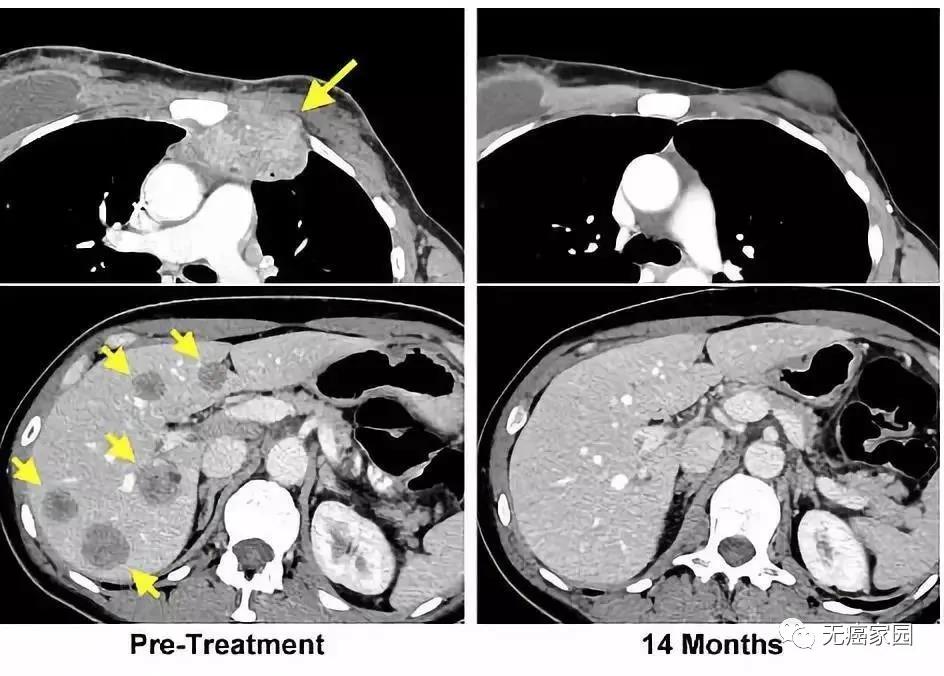

左图黄色箭头是治疗前肿瘤位置;右图是治疗结束14个月后的复查:肿瘤完全消失

Ms. Perkins被治愈这一事实给癌症患者及癌症疗法研究者带去了极大的鼓舞。虽然她只是一个个例。但是她体内转移性乳腺癌细胞已经检测不出这一事实,是一非常重要的结果。